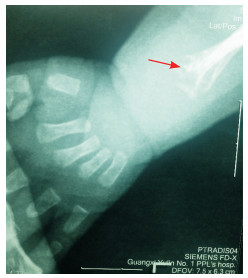

1 资料与方法 1.1 研究对象患儿,男,5个月。因体重不增4月余,气促、反应差5 d入院。既往因肺炎住院4次,因呼吸衰竭多次抢救治疗。患儿为第二胎第二产, 足月顺产出生,出生体重3 100 g,出生时无窒息史。人工喂养,新生儿晚期即有喂养困难,体重不增并逐渐下降。至今不会抬头、翻身。入院查体:体重2 590 g,身长56 cm。体温36.0℃,心率147次/min,呼吸59次/min。皮肤干皱,皮下脂肪消失,前囟5×5 cm,骨缝宽,枕部触诊乒乓球感。双耳位偏低,下颌小,呼吸急促、见吸气三凹征,胸骨凹陷,可见肋骨串珠,双侧桡骨弯曲畸形,双膝外翻畸形。母孕期体健,否认毒物、放射线接触史。否认近亲婚配及家族遗传病史。辅助检查:血常规WBC 13.1×109/L,余项正常;肝功能:谷丙转氨酶86 U/L(参考值9~50 U/L)、谷草转氨酶54 U/L(参考值15~45 U/L),余项正常;肌酸激酶(CK)正常;7次血钙波动在3.19~4.40 mmol/L(参考值2.08~2.60 mmol/L);5次碱性磷酸酶波动在9~17 mmol/L(参考值40~750 mmol/L);1, 25-二羟基维生素D3(VitD3)正常;甲状旁腺素3.5 pg/mL(参考值:6~80 pg/mL);降钙素22.1 pg/mL(参考值:0~18 pg/mL)。血串联质谱分析未见异常。尿气相质谱示4-羟基苯乳酸偏高。胸部X线片:支气管肺炎。左腕关节正位片:骨矿化不良,左侧尺、桡骨远端干骺端先期钙化带骨小梁模糊,并见干骺端不规则骨质缺损,未见骨化中心(见图 1)。胸腰椎正位X线片:各椎体骨质疏松、椎间隙窄、肋骨串珠及骨质密度普遍降低。

图 1 患儿5月龄左腕正位片 骨矿化不良,未见骨化中心;左侧尺、桡骨远端干骺端先期钙化带骨小梁模糊,并可见干骺端不规则骨质缺损(如箭头所示)。 |

HPP临床表型的异质性及影像学表现的多样性不影响X线作为HPP临床诊断的重要依据[15]。几乎所有HPP患者的X线均可见骨矿化不足、骨质疏松、类佝偻病表现。本例患儿左腕X有骨矿化不良,骨化中心消失,干骺端先期钙化带骨小梁模糊等表现;脊柱X线显示各椎体骨质疏松、肋骨串珠、骨质密度普遍降低,符合HPP的X线特点。